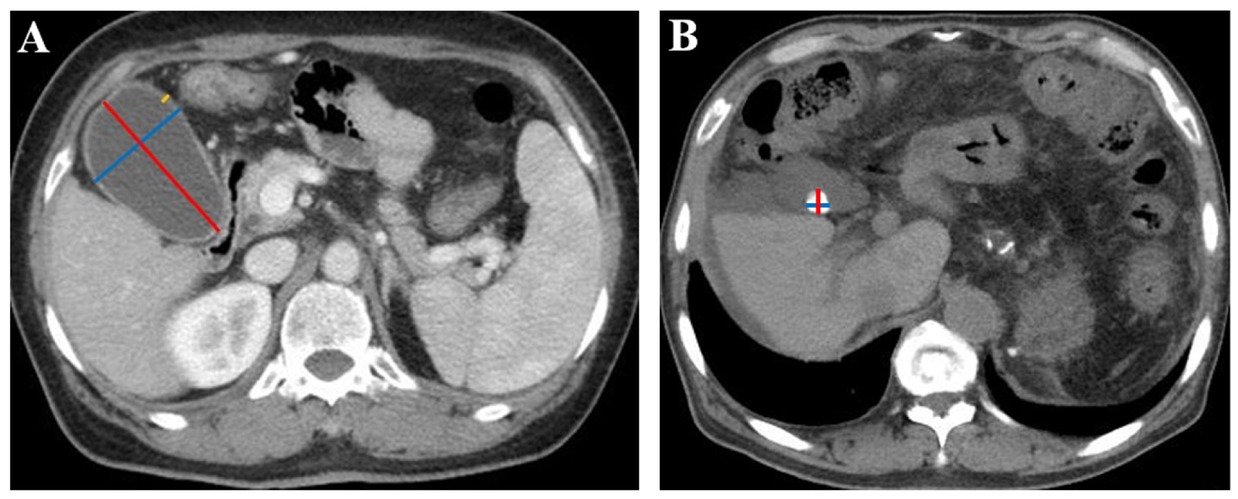

Two investigators independently reviewed all available CT images of each included patient, selected the specific layers, where the maximum length and width of gallbladder, the maximum thickness of the gallbladder wall, and the maximum length and width of gallstones were obtained, and then measured these parameters according to the standard methods as shown in Figure 1. A disagreement between them was resolved by discussing with another investigator to determine the most appropriate layer where the value measured should be maximal as the final value. Notably, all patients are routinely requested to be fasting before undergoing abdominal contrast-enhanced CT or MRI scan.

Gallbladder and gallstone parameters measured in CT images. (A) Measurement of gallbladder parameters in a 63-year-old woman with liver cirrhosis. The red line represents the maximum gallbladder length, the blue line represents the maximum gallbladder width, and the yellow line represents the maximum gallbladder wall thickness. The maximum gallbladder length was 77.6 mm, the maximum gallbladder width was 49.0 mm, and the maximum gallbladder wall thickness was 3.5 mm. (B) Measurement of gallstone parameters in a 65-year-old man with liver cirrhosis. The red line represents the maximum gallstone length, and the blue line represents the maximum gallstone width. The maximum gallstone length was 12.7 mm, and the maximum gallstone width was 12.4 mm. CT: computed tomography.